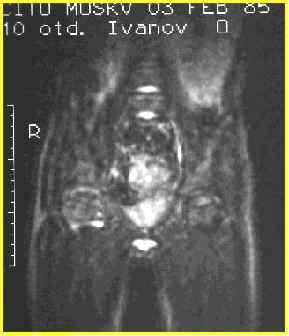

МР томограмма.

Асептический некроз головки правой бедренной кости.